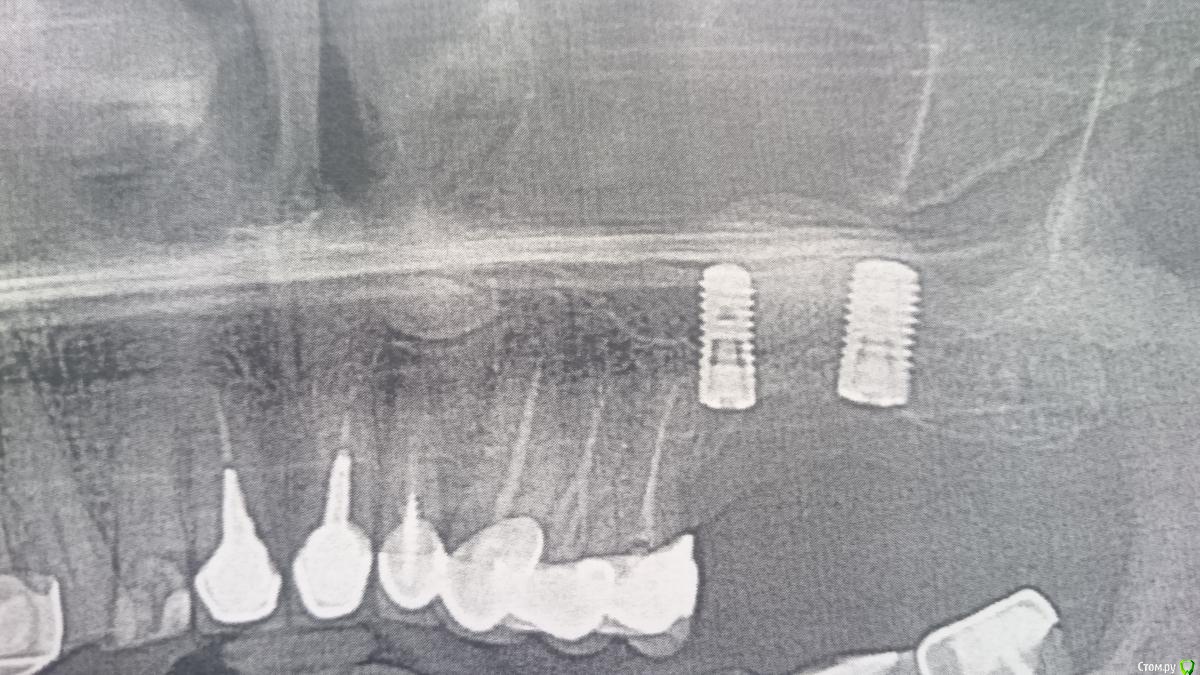

DrNice Опубликовано 27 октября, 2017 Поделиться Опубликовано 27 октября, 2017 Приветствую коллеги. Нужна инфа, какие нужны позиции заказать для протезирования на имплантах штрауман с винтовой фиксацией?У вас BL 4.1 и 4.8 это стандартные платформы, соединение RC. Заказываете все на стандартную платформу. 1 Ссылка на комментарий

vadyasti Опубликовано 27 октября, 2017 Автор Поделиться Опубликовано 27 октября, 2017 У вас BL 4.1 и 4.8 это стандартные платформы, соединение RC. Заказываете все на стандартную платформу. Спасибо, это я понял. А что нужно для техника заказать? И подходит ли к системе отвертка от астры или Израиля? Ссылка на комментарий

DrNice Опубликовано 27 октября, 2017 Поделиться Опубликовано 27 октября, 2017 Спасибо, это я понял. А что нужно для техника заказать? И подходит ли к системе отвертка от астры или Израиля?Зависит от мягких тканей и положения имплантов. Покажите фото во рту для начала. Техник смотрит куда выходит шахта и тогда вы принимаете решение, винтовая фиксация или цементная. Делайте индивидуализацию контура с помощью временных коронок на временных абатментах, потом уже индивидуальные абатменты. Отвертки не подойдут, ключ подойдет от любой корейской системы. Ссылка на комментарий